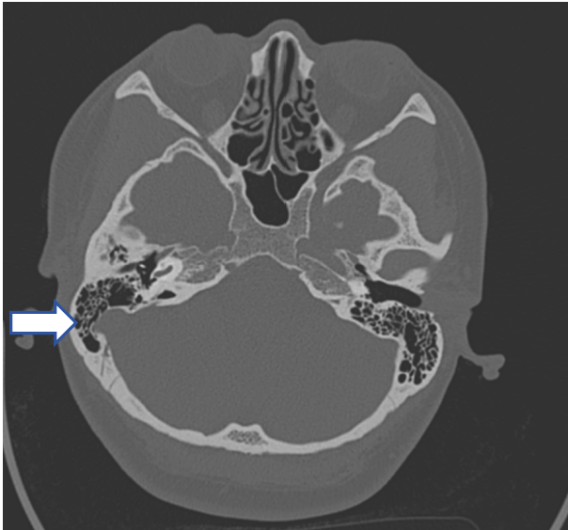

45岁的张女士,2周前出现左耳搏动性耳鸣,与心跳同步,压颈试验耳鸣声减轻。查体见左侧外耳道耵聍栓塞,完全堵塞,无法窥及鼓膜,右侧外耳道无异常。乳突无压痛。

完善CT示:左侧外耳道耵聍、乳突炎

初步诊断

血管性耳鸣,左侧耵聍栓塞

患者的搏动性耳鸣,可能与外耳道封闭放大血流声或局部血管受压、乳突炎症有关。通过取出耵聍后,患者耳鸣明显好转。